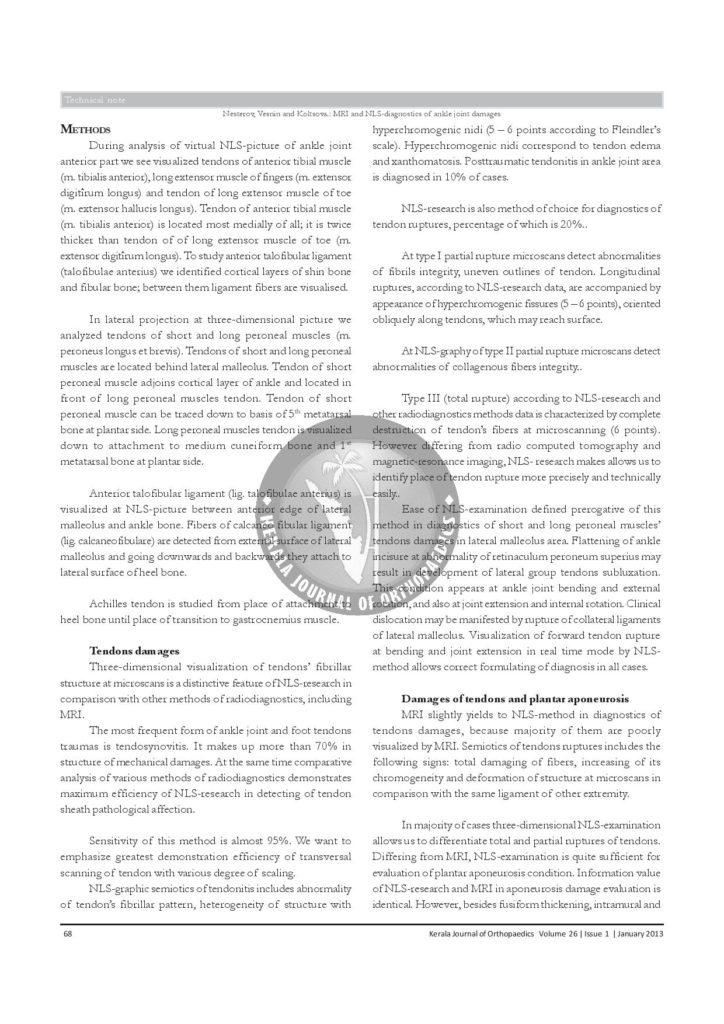

Diagnostyka MRI i NLS uszkodzenia stawu skokowego